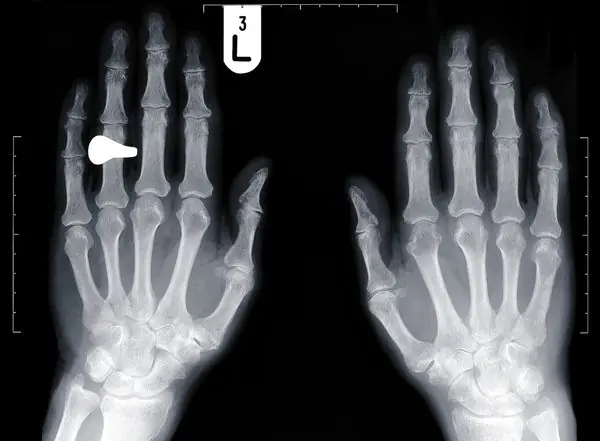

¿Por qué los dedos mayoría de los hombres del anillo son tan largas Es su dedo anular más largo o más corto que el dedo índice? La razón de la diferencia está en nuestras hormonas, un nuevo estudio en ratones muestra por primera vez. Antes del nacimiento, las hormonas sexuales estrógeno y testosterona genes de control que a su vez determinan longitud de los dedos, encontró el estudio. Al igual que nosotros, los ratones, naturalmente, tienen ambas hormonas en su cuerpo. (Obtener una visión genética.) Como resultado, la mayoría de los hombres tienen dedos anulares más largos que sus dedos índice, y lo contrario es cierto en las mujeres. Las diferencias en la longitud de los dedos han sido repetidamente relacionado con una serie de rasgos humanos, de la agresión a la habilidad musical a la orientación sexual. También hay conexiones con los problemas de salud tales como el autismo, la depresión, ataques cardíacos y cáncer Longitud de los dedos de una instantánea de la matriz? En general, los resultados sugieren que nuestra longitud de los dedos puede ser casi una "lectura" del equilibrio hormonal de una persona durante una ventana muy estrecha de desarrollo en el útero, dijo Cohn. Por ejemplo, si un hombre tiene un dedo índice más largo que el dedo del anillo, él pudo haber tenido una dosis elevada de estrógenos en algún momento de su desarrollo, lo cual no es necesariamente una mala cosa. Sin embargo, en algunos casos, estas irregularidades pueden llevar a enfermedades en la edad adulta. La exposición en el útero a sustancias químicas sintéticas que imitan o bloquean las hormonas, por ejemplo, se ha relacionado con problemas de salud en niños y adultos. Anteriormente, era difícil saber si la madre había sido expuesto a una sustancia durante el embarazo, que interrumpió la actividad de la hormona en su hijo. Ahora, "nuestros resultados sugieren un evento puede dejar una firma", dijo Cohn. Que "podría ser una herramienta útil" para averiguar la causa de una enfermedad, malformación, o incluso un rasgo de comportamiento. +1nfo:http://news.nationalgeographic.com/news/2011/09/110907-ring-finger-length-science-genes-sex-hormones-men-women/?source=link_fb20110908news-mensringfingers _______________________________________________________________________________________________________________